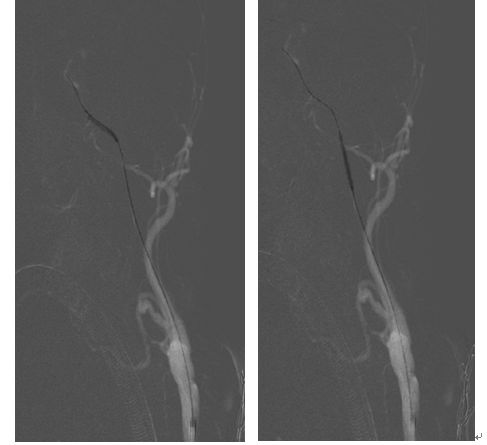

术前造影显示颈动脉C1-C4闭塞

颈动脉内膜剥脱后可见闭塞处血流缓慢。

近端闭塞处置入支架后,可见海绵窦段极重度狭窄

术中用小球囊2.5-20mm的球囊扩张海绵窦段狭窄处。

球囊扩张后,海绵窦段血流通畅。